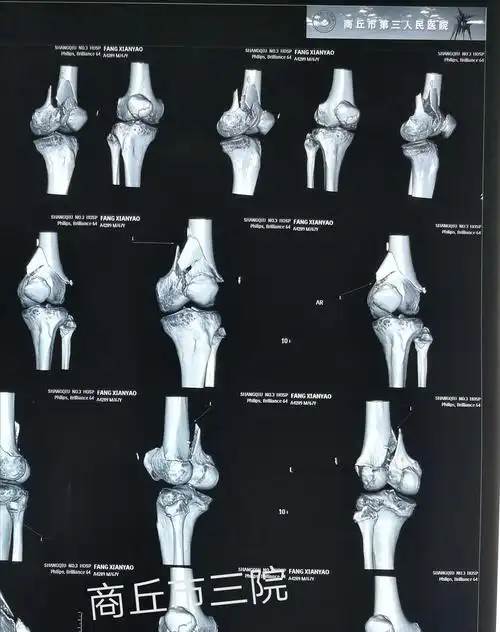

左股骨髁上,髁间粉碎性骨折

股骨髁间粉碎性骨折(c2型)